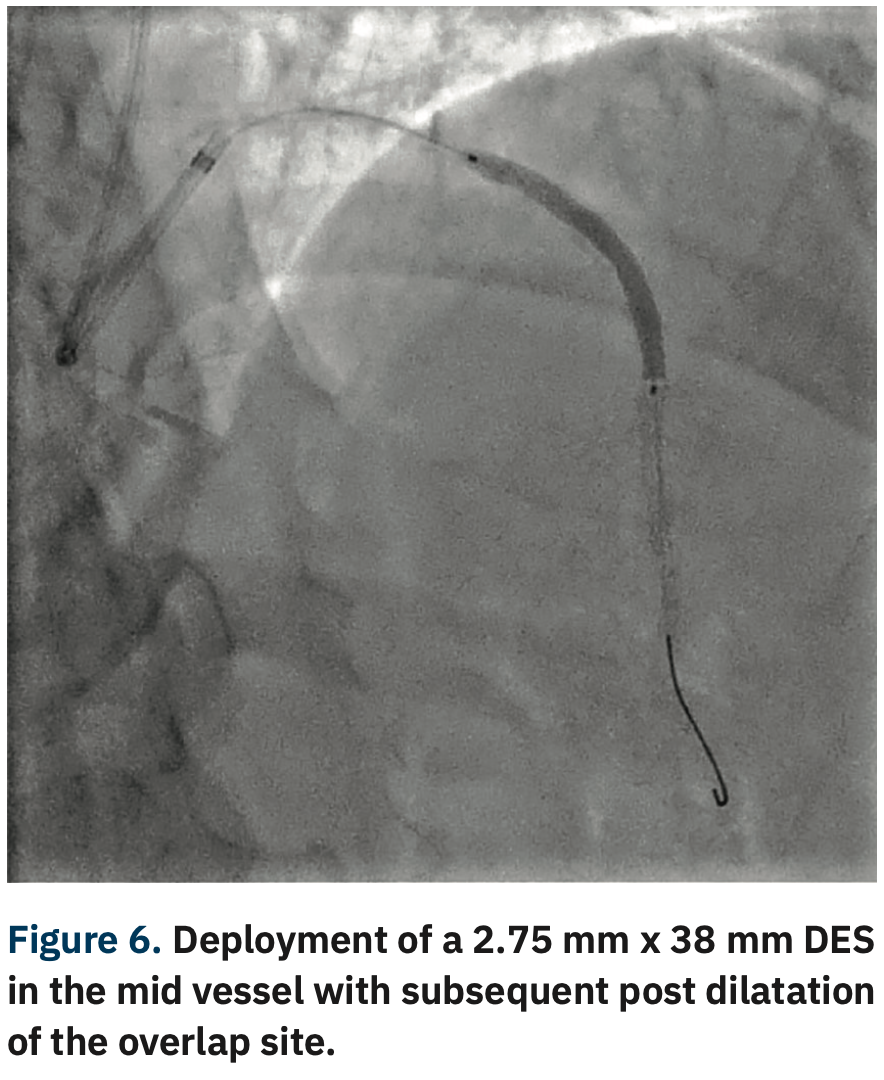

Like all centers, we are using more and more advanced imaging, but it is not uncommon for a lesion to be unpredictably difficult to dilate and more heavily calcified than is readily apparent on angiography. In those situations, with a lesion that will not dilate, it is necessary to have a method by which to modify the calcium, even though its presence was not anticipated. This is a particularly precarious situation for operators in non-backup settings. In the past, we would use oversized, non-compliant balloons and take them to very high pressures trying to achieve an adequate final stent result. In exceptionally rare cases, a handful of times over my 10 years here, we would even abort the case mid angioplasty and have to transfer the patient in a less than entirely stable fashion to the high-risk center. Calcium was our Achilles’ heel. We could always filter out the obviously high-risk cases, but there will always be a very small fraction of cases that do not have readily apparent calcium and are non-dilatable. IVL, from a safety standpoint, has been a game-changer for us not only in these cases, but also for cases with readily apparent calcium that otherwise would have required atherectomy. With the use of IVL, we are now at a point where the only cases that we have to either transfer or stage are non-crossable lesions: cases where you can get a wire but not a balloon across, and these are fairly rare.

With the ability to more aggressively treat calcium here at our primary site with IVL, there has been a big uptick in our utilization of intervascular imaging such as intravascular ultrasound (IVUS). We are bringing in optical coherence tomography (OCT), with the idea that we will image a much higher fraction of our cases, because of this concept of unappreciated calcification. When we see either moderate or worse calcium, or have a recalcitrant lesion or lesion that is not dilating normally, we are quick to pull the IVUS imaging catheter out in order to assess the arc, length, and width of the calcium. Post IVL, we will generally reassess the lesion to confirm fracture of the calcium. We don’t require IVUS post IVL for stenting, but it definitely is something that makes us feel good about moving forward with stent implantation. More and more, intravascular imaging is going to be a marketable quality indicator. If you are only doing a small percentage of intravascular imaging, I think you are going to be perceived as a lesser quality program. There has been a longstanding resistance to adopting a higher utilization of intravascular imaging, because of the combination of cost and time. I wish that CMS would see the benefit and create a situation where there are not negative financial incentives to doing imaging.

Yes. IVL turns a difficult PCI into an easy PCI with a device that’s easy to use and financially viable for the hospital. The safety issue can’t be overemphasized. Cases that previously required the use of buddy wires, and secondary and tertiary balloons, add time and complexity. Balloon ruptures are also more frequent. You then have to use new balloons and the chance of having a complication such as a perforation goes up. All it takes is one perforation where you have to do a pericardiocentesis and salvage an emergency situation to see the value proposition of IVL. The cost of ambulance transfers and the cost of all the additional ancillary staff for a secondary procedure is also immense. Optimal procedural results also reduce readmission rates, which brings cost savings and quality improvement in terms of outcomes. IVL is a win across the board, for patients, providers, and administration.